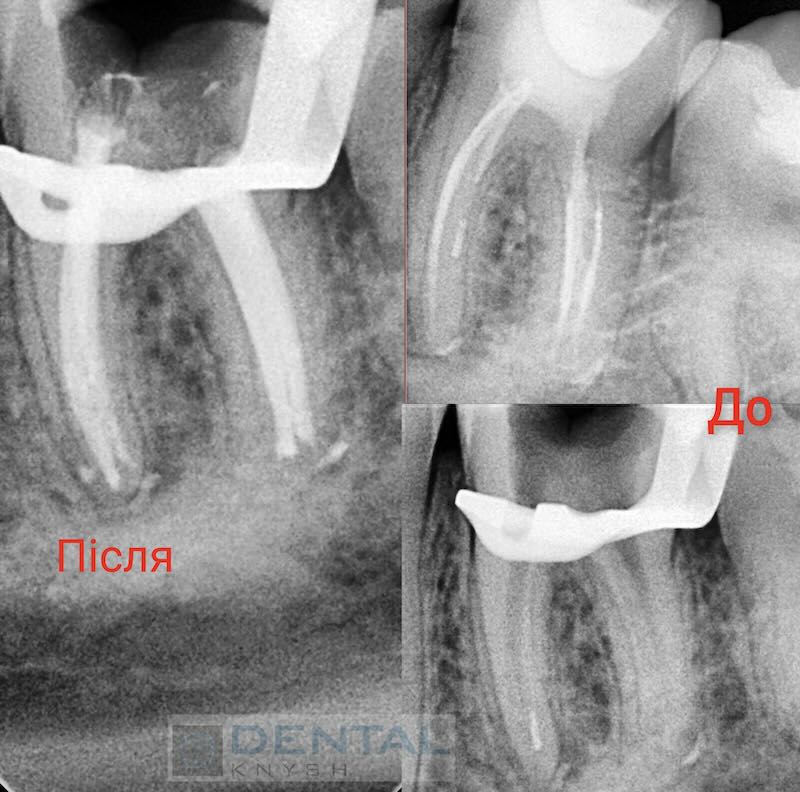

„Leczenie kanałowe pod mikroskopem daje najlepsze wyniki leczenia bez żadnych zastrzeżeń.

Nie każda klinika ma mikroskop do leczenia stomatologicznego, ale w przyszłości mikroskop będzie koniecznością. Im lepszy widok pola pracy, tym lepsze wyniki leczenia.

Początkowo fotele dentystyczne były w tym celu uzupełniane lampami, ale wraz z pojawieniem się mikroskopów stomatologia weszła w nowy etap rozwoju”.

Fotorelacje